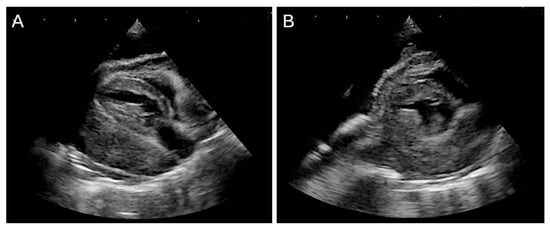

2.2. Referral and Diagnostic Evaluation